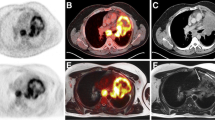

According to histopathology, T staging was correct with transverse T2 BLADE in 69 % of patients, with coronal HASTE in 67.9 %, with contrast-enhanced T1 FLASH in 59 %, with TrueFISP in 57.1 %, with non-enhanced T1 FLASH in 50 %, with transverse T1 3D Dixon VIBE in 45.2 % and with coronal T1 3D Dixon VIBE in 47.6 % (Figs. 1 and 2; Online resource 1). While the number of inaccurate evaluations of extrapulmonary spread were comparable among all sequences, inaccurate lesion detection and tumour site estimation were especially problematic with T1 FLASH and with coronal and axial T1 3D Dixon VIBE (Table 1).

A 64-year-old patient with squamous cell carcinoma in the left lower lobe: a–c PET/CT, d–j PET/MR. While the histopathologically confirmed pT1a lesion is visualized very well on the PET images (c, f), the non-enhanced CT image (a), the T2 BLADE images (d, g, arrow) and the contrast-enhanced T1 FLASH image (h, arrow), it is not detectable on the non-enhanced T1 FLASH image (I) or the T1 3D Dixon VIBE image (j), rendering exact local tumour staging impossible

An 84-year-old patient with squamous cell carcinoma in the right upper lobe: a–c PET/CT, d–j PET/MR. On histopathological work-up, the maximum tumour diameter was 33 mm. As no pleural invasion was present (d, e), pathological T stage was 2a. While correct T staging was possible with a maximum tumour diameter of 31 mm on T2 BLADE images (d, h) and 38 mm on T2 HASTE images (j), underestimation of the maximum tumour diameter on T1 3D Dixon VIBE images (g, i; 20 mm in axial orientation) led to downstaging with this MR sequence